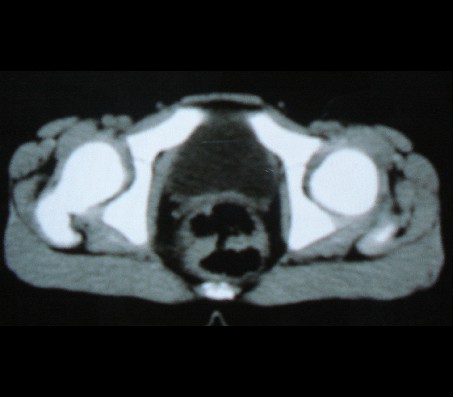

标题: PED0942:女性,8岁,B超提示盆腔病变,请会诊! [打印本页]

标题: PED0942:女性,8岁,B超提示盆腔病变,请会诊!

畸胎瘤

考虑畸胎瘤可能性大!

建议增强进一步检查除外畸胎瘤。

考虑畸胎瘤可能。

考虑畸胎瘤可能

考虑畸胎瘤可能性大.

考虑畸胎瘤可能性大。

畸胎瘤可能性大。

畸胎瘤可能性大!

考虑畸胎瘤可能大,建议进一步检查。